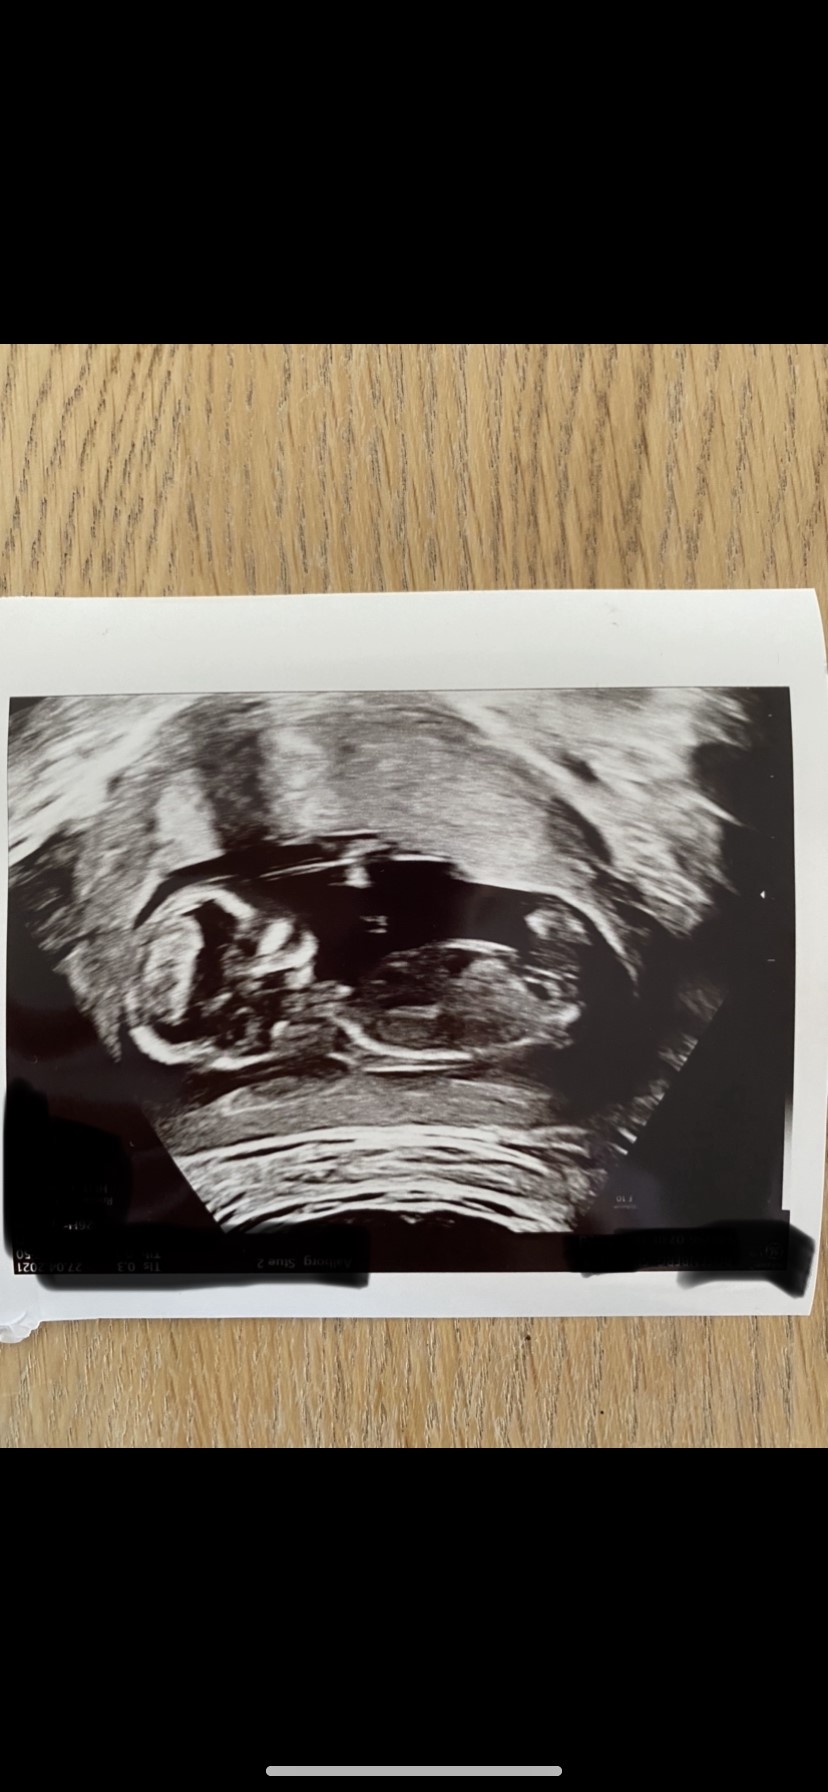

Er der nogen der tør gætte på, om vi venter en lille dreng eller en lille pige?

Jeg er noget i tvivl om, hvorvidt det egentligt er nubben, der kan ses foroven (til skanningen lignede det mere det øverste af lårbenet og bevægede sig sammen med resten af benet) hvis det er det tænker jeg selv dreng og hvis ikke så ligner det måske en lille pigenub længere nede.

Vedhæftede fotos (klik for at se i fuld størrelse)

Det sidste billede ligner meeeeget en dreng